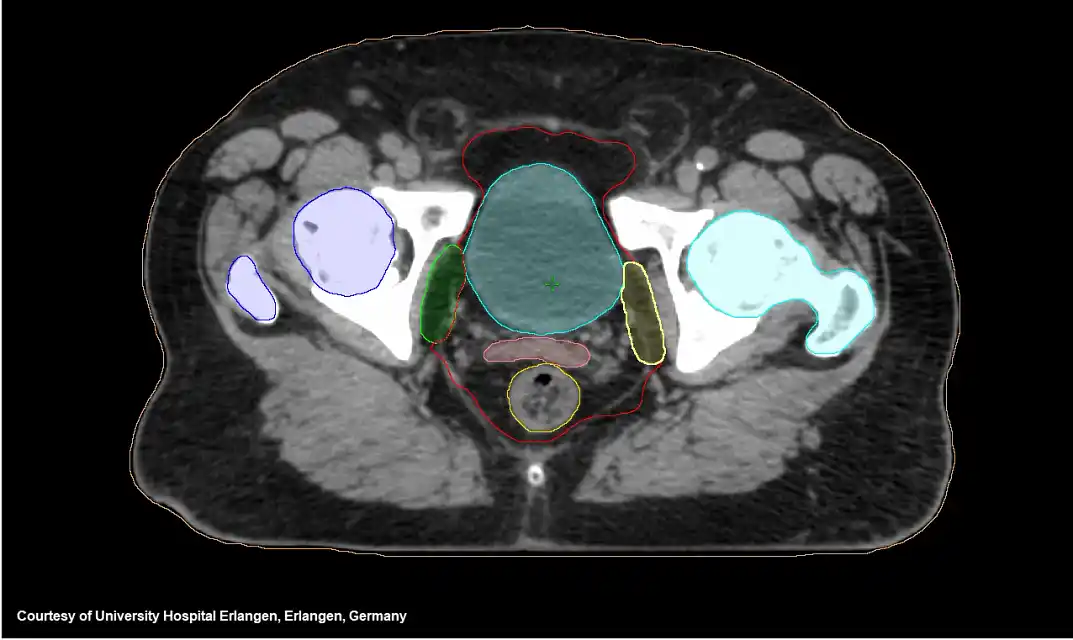

AI Rad Companion Organs RT Varian

Varian Brings Machine Learning to Proton Treatment Planning on sale, Varian integrates machine learning into proton treatment planning on sale, cancer Varian makes cancer care affordable to all Indians with AI on sale, RapidPlan Machine Learning Brings Intelligence to Cancer Care on sale, Machine Learning at Northwell Health Using RapidPlan to Develop on sale, Products Varian on sale, Artificial Intelligence Greatly Speeds Radiation Therapy Treatment on sale, Radiotherapy Varian on sale, Products Varian on sale, Introducing Halcyon An Innovative Treatment Platform Varian on sale, Products Varian on sale, Google chief economist Hal Varian offers machine learning insights on sale, Using federated data sources and Varian Learning Portal framework on sale, Data science machine learning ML artificial intelligence AI on sale, Adaptive Therapy Varian on sale, Artificial Intelligence and Antitrust Hal Varian PPT on sale, Radiotherapy Varian on sale, Varian Machine Learning 2024 www.chop rite on sale, Swedish Cancer Institute brings adaptive radiation therapy to the on sale, First ever Refurbished Varian TrueBeam is Installed in Latin on sale, Refurbished Varian TrueBeam Linear Accelerator ROS on sale, Varian Medical Systems ASTRO Exhibit Spotlights Technology on sale, AI Enabling Standardization Radiation Oncology Michigan on sale, Varian Identify System Best Radiation Therapy Little Rock CARTI on sale, Awards for Accelerators Tech from Medical Treatment to Machine on sale, Edge Veterinary Oncology Varian on sale, Deep Learning Methods for Image Guidance in Radiation Therapy on sale, Varian Machine Learning 2024 www.chop rite on sale, Bias Variance Tradeoff Impact on Machine Learning Performance on sale, AI Rad Companion Organs RT Varian on sale, Products Varian on sale, Left Varian TrueBeam LINAC and right its MLC comprised of on sale, cancer Varian makes cancer care affordable to all Indians with AI on sale, Varian Announces Collaboration Agreement with COTA Inc on sale, Varian LinkedIn on sale.